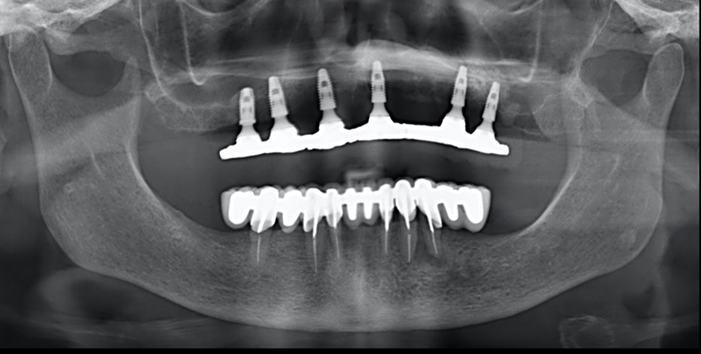

Case 4: a 38-year-old patient presented a class III maxillomandibular relationship with retention of multiple permanent and supernumerary impacted teeth. The teeth in the mouth were deciduous, supernumerary. Due to the number of impacted teeth and the size of the roots of the teeth in the mouth, orthodontics was contraindicated. Initial treatment was performed using Le Fort I osteotomy for maxillary advancement and bilateral sagittal osteotomy of the mandibular ramus for setback (figure 13). After 6 months under general anesthesia, the teeth in the mouth were removed, and 4 implants were installed in the maxilla and 4 in the mandible, respecting the remaining included teeth with the exception of the implant installed in the region of tooth 21 that transfixed the crown of the one that was included.

Two protocol-type prostheses in immediate loading were installed. In the 18-month control, prosthetic normality was observed and in the imaging examination, normality was observed in the 8 implants and the remaining impacted teeth (figure 14).

Case 5: a 62-year-old patient with a complete denture sought treatment with osseointegrated implants seeking a fixed prosthesis. In the imaging exams, it was observed that the upper left canine was included in a vertical position, extending from the midline to approximately tooth 24 (figure 15).Six implants were installed, with the most anterior fixation of the left maxilla being installed by milling the impacted tooth on purpose. After 90 days of osseointegration, the implants were reopened and a protocol-type prosthesis was made. After 18 months of function, no type of clinical or radiographic change was found about the implants or the impacted tooth, nor were any prosthetic complications found (figure 16).